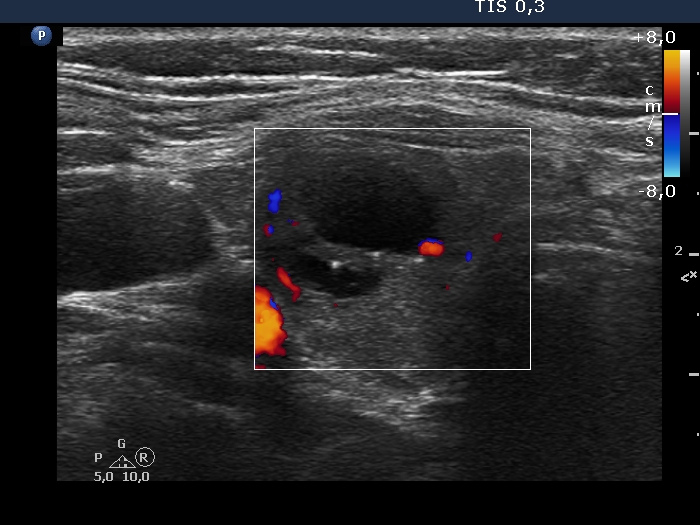

Ultrasonography. Except for the lesion which was previosuly cytologically investigated, the pattern remained unchanged. The lesion in question became cystic and was composed of two chambers. In the tissue part separating the two chambers, hyperechoic granules have appeared. These were mostly related to ventral cystic areas, therefore, they should be regarded as back wall figures.

Ultrasonography. The previously cystic lesion has spontaneously decreased in size, the cystic fluid has disappeared. However, the hyperechogenic foci were still visible. If we had only seen this current study, we would have had to regard these echogenic granules microcalcifications.